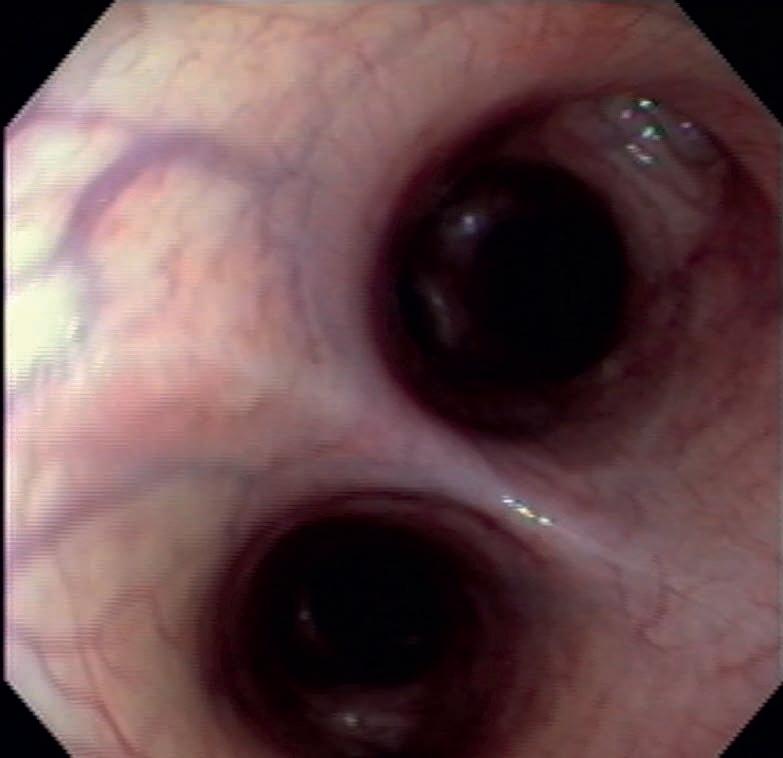

Fig1. Endoscopia de bronquios hiperémicos con presencia de fluido. Cortesía del MVZ León Ramírez.

Los signos y síntomas del SDRPN se asocian a errores en la adaptación morfo funcional durante el cambio del sistema respiratorio fetal al del potro neonato. Dichos errores inducen al incorrecto intercambio gaseoso en la vida extrauterina. De manera resumida estos son:

a. Inadecuado desarrollo mesenquimal del árbol bronquial.

b. Alteraciones en la síntesis o falta de glucógeno y de surfactante alveolar. Fig 1.

c. Incorrectas adaptaciones histológicas de la etapa "glandular" a la etapa "canalicular" del árbol bronco alveolar.